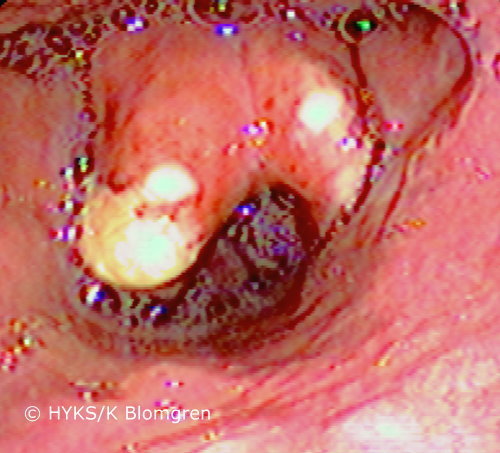

Epiglottitis

Epiglottitis. In epiglottitis, the epiglottis is not always red but it may also be covered by a membrane or purulent discharge. This patient underwent tracheostomy.

Picture: Karin Blomgren / HUCH/Eye and Ear Hospital